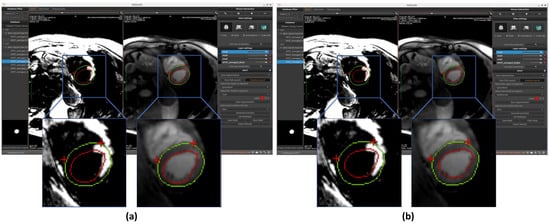

The first function enables automated segmentation of LV regions of interest in cardiac MRI. Within our workspace, users initially upload paired BR- and BL-LGE images, which are automatically displayed in adjacent viewing panels. The system offers three distinct segmentation targets: LV endocardium, epicardium, or full myocardial wall. Following the AI-powered SPOT framework, users may select between two deep learning architectures: a U-Net-based model or a MedFormer-based alternative. Both models are evaluated and produce correct results, as illustrated in Figure 5. Extensive testing shows that the MedFormer model demonstrates slightly better performance than the U-Net model, particularly at the basal and apical levels. Nevertheless, both models remain suitable for providing reliable references in our application. As previously detailed in Section 2.2, both models are implemented using the ONNX Runtime library for optimized inference. These models were trained on a dataset of approximately 300 patients (over 5000 images) who were referred for cardiac MRI between August 2022 and April 2023 due to known or suspected ischemic heart disease, enabling reliable automated region extraction. All participants underwent SPOT sequence imaging. Patients were excluded if they were under 18 years of age, had a history of allergic reaction to gadolinium-based contrast agents, severe renal failure, non-MR-conditional implants, inability to lie supine for 50 min, were pregnant or breastfeeding, or could not provide informed consent. All imaging was performed on a 1.5 T clinical MRI scanner (Magnetom Aera, Siemens Healthcare, Erlangen, Germany). These two model architectures will be presented in subsequent sections.

The results of segmentation of endocardium and epicardium by using the model U-Net are shown in Figure 5a.

Results of endocardium and epicardium segmentation using the Medformer model are shown in Figure 5b.

This model, like other AI modules in our workspace, was implemented using the ONNX Runtime environment to ensure high-performance inference. Final prediction outputs are visualized on the corresponding MRI images (see Figure 5), enabling users to verify model performance through anatomical overlays.

Figure 5. Automated segmentation of the left ventricular endocardium (red circle) and epicardium (green circle) performed on BR-LGE images using (a) U-Net and (b) MedFormer models. Contours are then propagated onto BL-LGE images allowing for scar analysis. Landmarks detection with a U-Net based model was applied in both cases on BR-LGE images to localize the right ventricular (RV) insertion point region within the myocardial muscle (two red crosses).